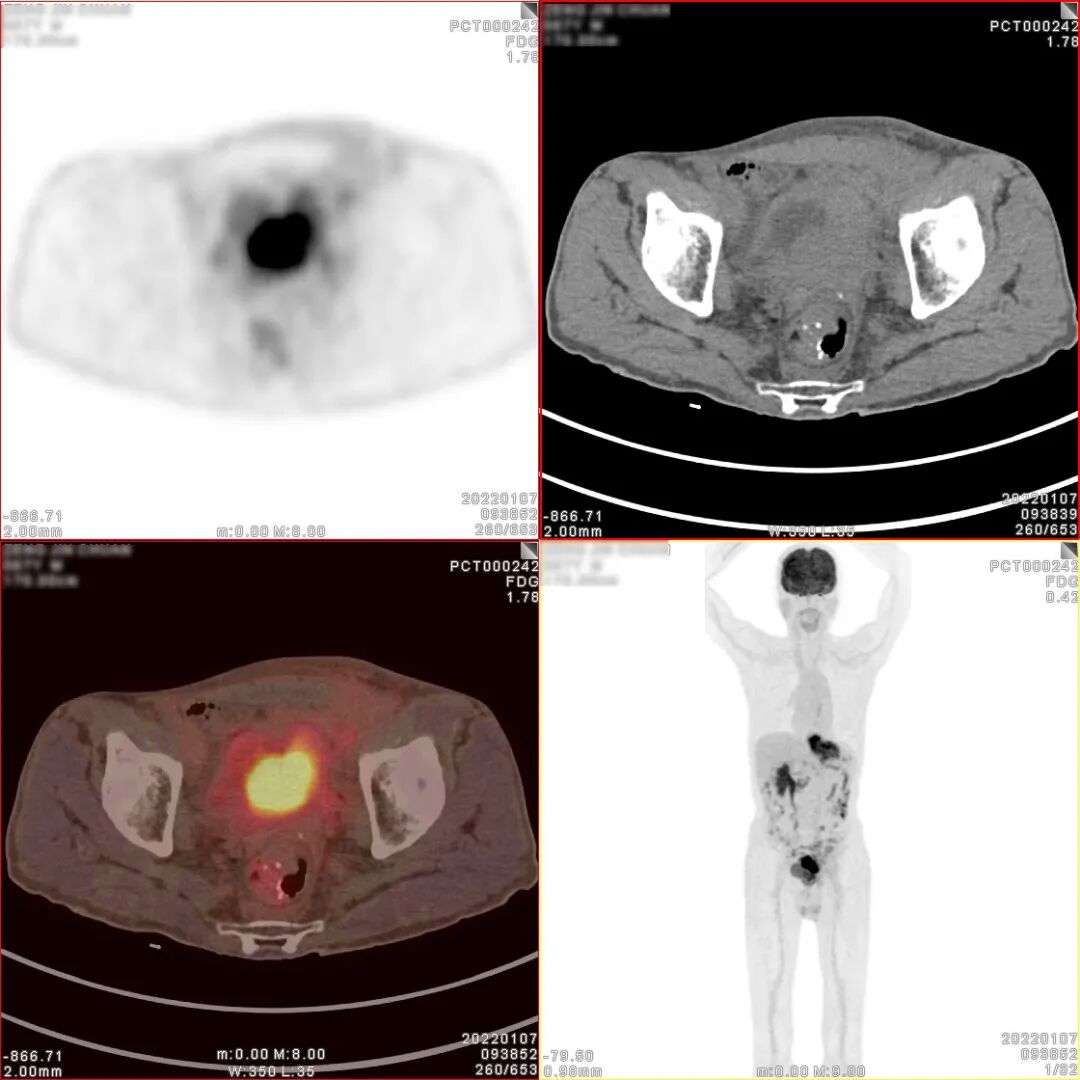

18F-FDG PET/CT检查图像

胃癌术后、化疗后,胃术后缺如,CT 见食管下段与肠道吻合口区软组织明显增 厚,密度较均匀,边缘欠清,PET 于相应部位可见不规则形放射性异常浓聚影,大小 约 71×27×63mm,SUVmax 为 9.5。CT 于左下腹部肠系膜上可见结节状密度增高影, 大小约 14×8mm,密度较均匀,边缘欠清,PET 于相应部位可见结节状放射性异常浓 聚影,SUVmax 为 4.9。CT 见腹盆腔其他部位肠系膜密度稍增高,边缘模糊,PET 于 相应部位未见明显放射性异常浓聚影。CT 见膀胱顶壁、左侧壁、左后壁及膀胱三角 区软组织明显增厚,密度较均匀,边缘欠清,堵塞双侧输尿管下段膀胱入口,并向 下与前列腺分界不清,PET 于增厚的膀胱壁内可见不规则形放射性异常浓聚影,大小约80×34×47mm,SUVmax 为 30.3;CT 见前列腺体积不大,其内可见多个小斑点状 高密度钙化影,PET 于前列腺内可见块状放射性异常浓聚影,大小约 39×36×35mm, SUVmax 为 6.9。CT 于盆腔内右侧髂外血管旁可见稍肿大淋巴结,大小约 10×7mm, PET 于相应部位可见结节状放射性异常浓聚影,SUVmax 为 2.9。

PET/CT诊断:

1、胃癌术后、化疗后,食管下段与肠道吻合口区软组织明显增厚,代谢增高, 考虑肿瘤复发病灶;

2、膀胱顶壁、左侧壁、左后壁及膀胱三角区不规则形代谢增高影及前列腺内块 状代谢增高影,考虑膀胱癌并侵犯前列腺;

3、左下腹部肠系膜上结节状密度增高影,代谢增高,考虑转移灶;腹盆腔其他 部位肠系膜密度稍增高,未见代谢增高,请结合临床追踪复查以排外低代谢腹膜 转移灶的可能;

4、盆腔内右侧髂外血管旁稍肿大淋巴结,代谢稍增高,不排外淋巴结转移灶的可能。